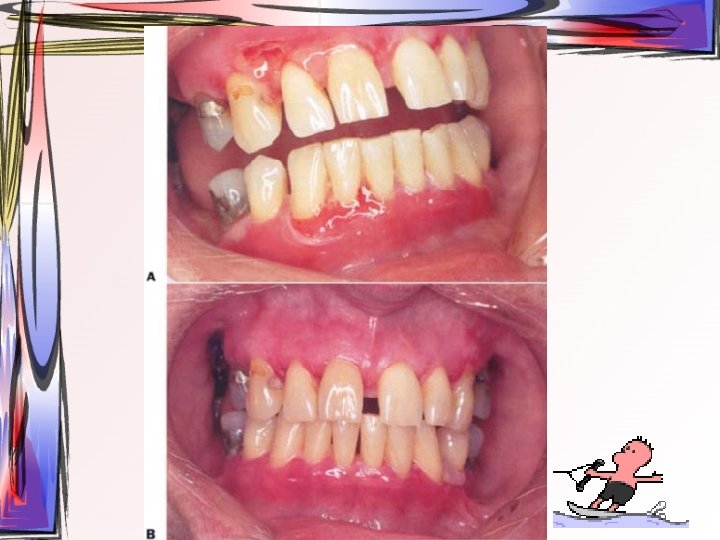

PEMPHİGUS VULGARİS • intraepiteliyal ayrılma ile karakterize mukokutanöz bir hastalık • akantolizis • kabarcıkların ülsere olması sıvı kaybı, elektrolit dengesizliği ve ağrılı bir tablo ortaya çıkar • desmozom komponentlerine karşı autoimmün reaksiyon yer almaktadır

• Bülleri takiben ülser oluşur • % 60 ilk belirtiler oral bölgede (önce ağızda başlar, en son ağızda iyileşir) • Klinik olarak sağlıklı gözüken mukoza üzerine hafif bastırarak sürtme ile epitelde ayrılma ve bül oluşur (Nikolsky belirtisi) • Deri lezyonu

• Cinsiyet ayrımı yok • en çok 4. ve 5. dekatlarda (geniş görülme aralığı) • Pemphigus vulgarise – – Myastenya gravis Lupus erithematozus Romatoid artirit Sjögren sendromu • Kortikosteroidlerin tedavi alanına girmesinden önce prognozu kötü olan bir hastalıktı. • Kortikosteroid tedavisiyle ölüm oranı %8 -10’a kadar düşmüştür. Bu da genellikle uzun süre kullanılan sistemik kortikosteroidlerin yan etkileri sebebiyledir.